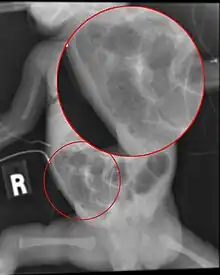

Diagnosis is usually suspected clinically, but often requires the aid of diagnostic imaging, most commonly radiography, which can show the intestines and may show areas with dead tissue or a bowel perforation.[18] Specific radiographic signs of NEC are associated with specific Bell's stages of the disease:[19]

- Specific radiologic signs (pneumatosis intestinalis or portal venous gas)

- Severe radiologic signs (pneumoperitoneum)

Ultrasonography has proven to be useful, as it may detect signs and complications of NEC before they are evident on radiographs, specifically in cases that involve a paucity of bowel gas, a gasless abdomen, or a sentinel loop.[21] Diagnosis is ultimately made in 5–10% of very-low-birth-weight infants (<1,500g).[22]

Alimentary tract of infant showing intestinal necrosis, pneumatosis intestinalis, and perforation site (arrow) (autopsy)

Close-up of intestine of infant showing necrosis and pneumatosis intestinalis (autopsy)

Diagnosis of NEC is more challenging in premature infants, due to inexplicit symptoms and radiographic signs. The most preterm infant is at highest risk of developing NEC.[23]